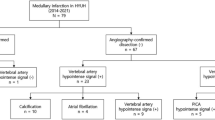

On SE-T1WI, a high-signal area was observed within or along the vertebrobasilar artery without abnormality on DSA/CTA in six cases (eight sites), which was considered a false-positive finding. No such finding was noted on 3D-BB-T1WI in any of the cases (Fig. 2).

Case 12. A 47-year-old man with sudden headache. MRI was obtained 9 days after onset. SE-T1WI (a) shows a high-intensity intramural haematoma of the right VA (arrow). Iso- to high signal is also observed in the left VA (arrowhead), which appeared normal on DSA and CTA. 3D-BB-T1WI (b) demonstrates the relationship between the intramural hematoma and the lumen. An axial reformatted 3D-BB-T1WI (c) shows the characteristic crescent shape of a haematoma (arrow). In 3D-BB-T1WI, the high-signal area is not noted in the left VA

Overall, 3D-BB-T1WI yielded better distinction of intramural haematomas compared to other sequences. Furthermore, iso- to high signal was observed on SE-T1WI in arteries that appeared normal on CTA/DSA in six cases (Fig. 2). These findings were considered flow artefacts because such signals were not noted on 3D-BB-T1WI in any of the cases. These results indicate that spatial presaturation alone may be insufficient to completely suppress the signal from inflowing blood on SE-T1WI. In 3D-BB-T1WI, suppression of the intravascular signal due to a lower refocusing flip angle and flow-sensitizing gradients (sensitized flow compensation) [13, 14] was helpful in better distinguishing haematomas than either SE-T1WI or MRA.